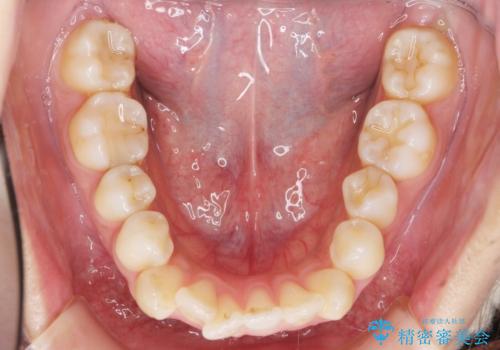

ガタつきと口元の改善 抜歯を伴うワイヤー矯正

- 唇の閉じづらさと、前歯のがたつきの改善を希望され来院されました。

抜歯を行わなくてもなんとか並べられる歯並びですが、唇の閉じづらさをしっかりと改善するため抜歯を伴うマルチブラケット矯正を行うこととしました。

前歯をしっかりと後方に引いたことで、唇は閉じやすくなり、仕上がりに満足いただくことができました。